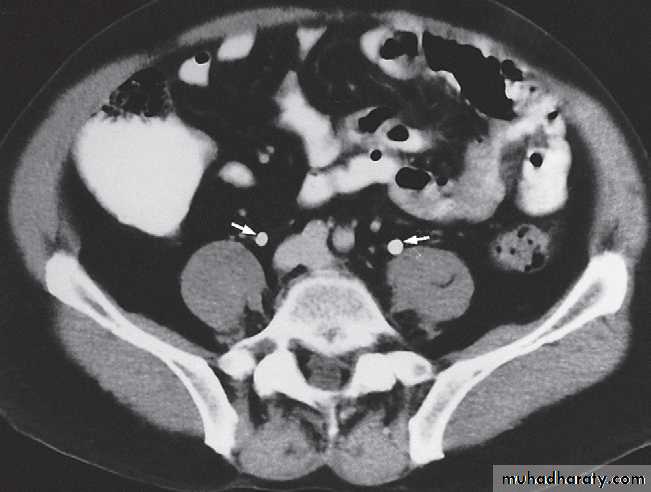

The principles of both techniques are similar. Firstly, ‘non-contrast’ imaging of the renal tract is required, in order to identify all renal tract calcifications. In some case, where the clinical question relates to renal calculi, the non contrast CT may be sufficient (known as the ‘CT KUB’).

-Plain film in intravenous urogram: it used to Identify all calcifications. Decide if they are in the kidneys by relating them to the renal outlines , calcification seen in the line of the ureters or bladder must be reviewed with post contrast scans, to determine whether the calcification lies in the renal tract. Note that calcification can be obscured by contrast medium and stones are missed if no plain film is taken.-Films taken after injection of contrast medium Kidneys

CT is initially performed without intravnous contrast medium (non-contrast CT or ‘CT KUB’) to identify calcification .indication and include: